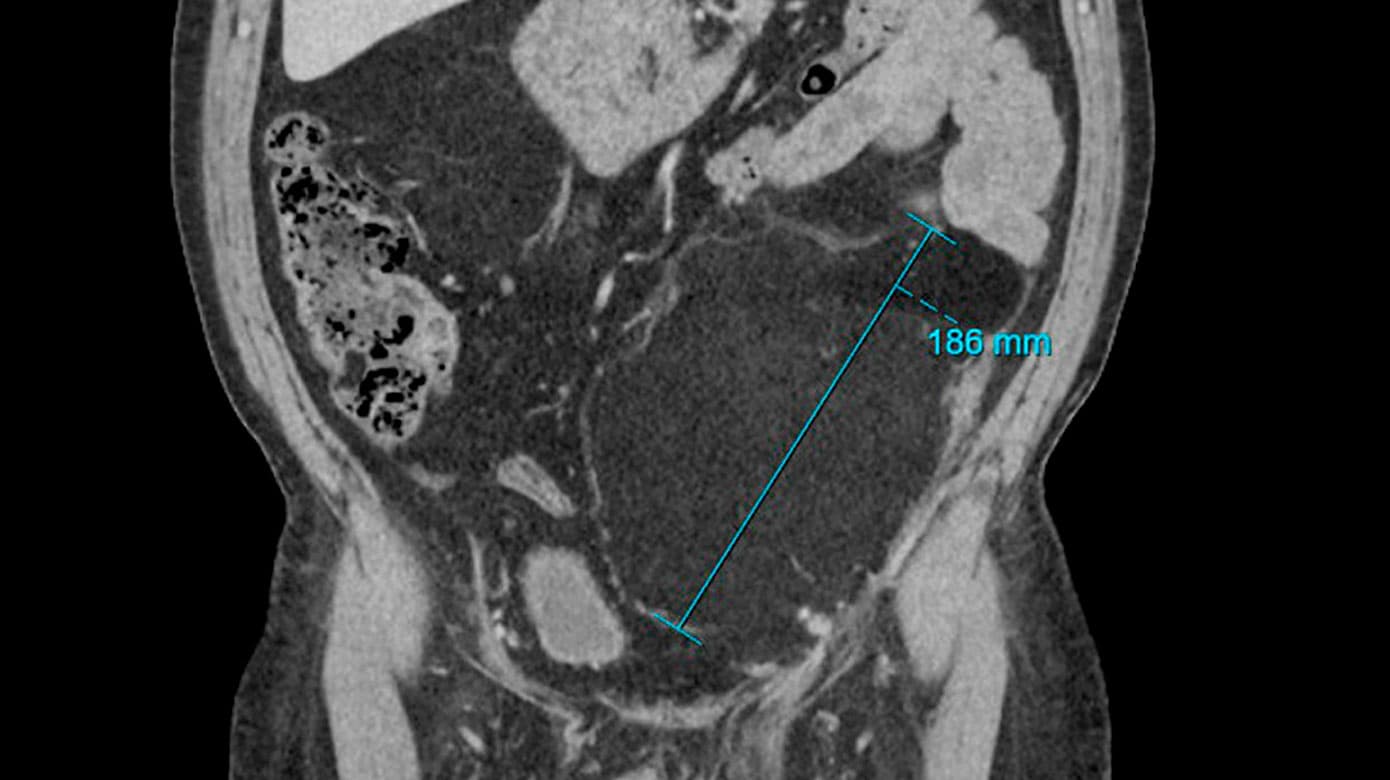

Patienten blev udredt med CT, hvor man fandt en stor tumor i venstre hemiskrotum samt i retroperitoneum. Tumoren kommunikerede via ingvinalkanalen og strakte sig op mod venstre nyre (Figur 1).